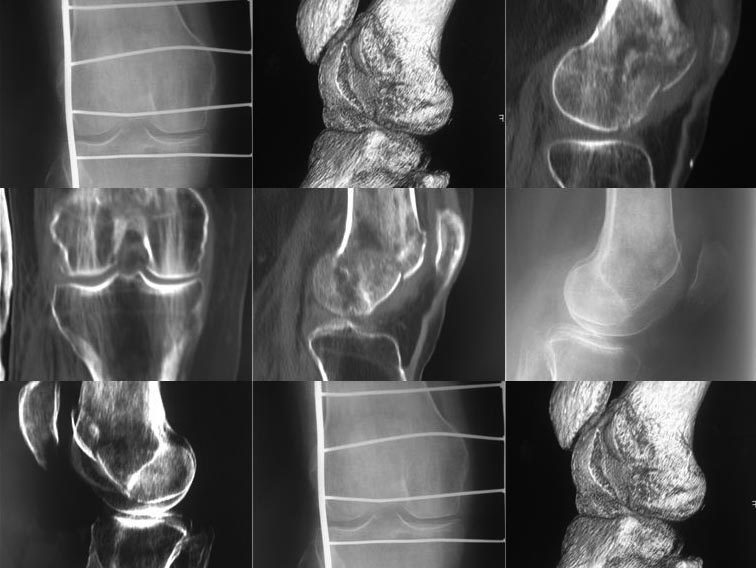

Добрый день, уважаемые коллеги! Помогите определиться с тактикой. Поступила женщина 48 лет, внутрисуставной перелом латерального мыщелка бедра.

Выполнили КТ.

Мне кажется здесь импрессионный перелом наружного мыщелка в результате прямой травмы в сустав. Для определения лечебной тактики не хватает данных. Некоторые снимки повторяются. Аксиальные срезы (поперечные) более информативны и надо добавить 3Д снимки в других ракурсах.

Очень странный перелом, механизм - или прямой удар в область латерального мыщелка при согнутом колене, или (на мой взгляд, вероятнее) переразгибание с латеральной девиацией, в таком случае мыщелок сплющился о передний край большеберцовой кости. Нет ли повреждения задней крестообразной связки? И нету ли в мыщелке какого-нибудь нехорошего очага? Кисты или метастаза? Что-то больно похоже на патологический перелом.

Если механизм травмы-прямой удар, то скорее всего коленный сустав был согнут на 90 градусов и более, и удар пришелся бы в область надколенника,и через него в мыщелок бедра.

С моей точки зрения на представленных снимках импрессия располагается в не нагружаемой суставной поверхности мыщелка бедра а , поэтому каких-то абсолютных показаний к остеосинтезу не нахожу. Если только с целью востановления бедренно-надколеникового сочленения.